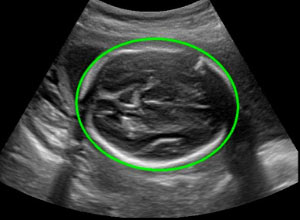

ПРИМЕРЫ ВИЗУАЛИЗАЦИИ АППАРАТА

(Вы также можете приехать и протестировать аппарат в нашем шоуруме)

Брюшная полость и линейный датчик:

Автоизмерение ТВПп

Автоматическое оконтуривание и измерение толщины воротникового пространства (воротниковой зоны) плода по срединной проекции.

Автофетометрия плода

Автоматическое оконтуривание основных костей плода одним нажатием с возможностью последующей регулировки полученного значения.